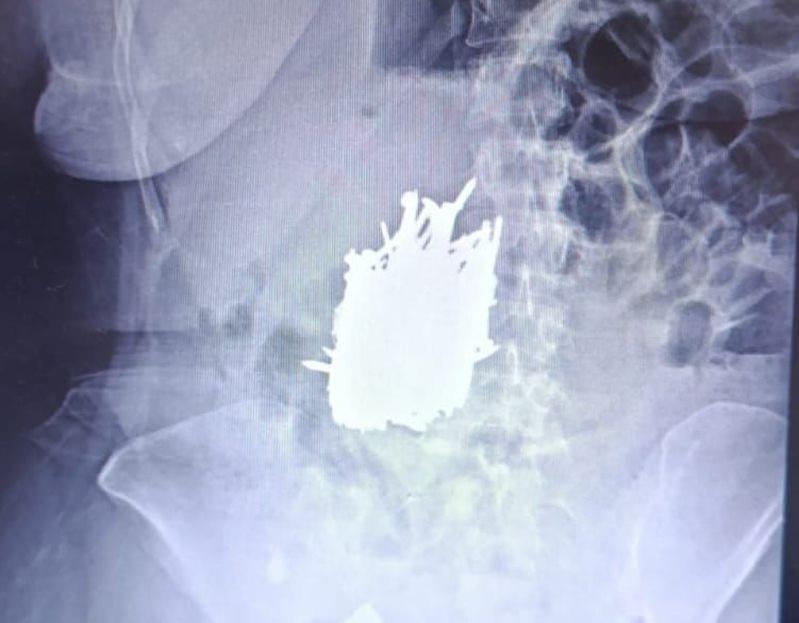

Mersin’in Faziletli ilçesinde yaşayan 52 yaşındaki zihinsel engelli A.K.’yi karın ağrısı şikayetiyle hastaneye götüren yakını duyduklarına inanamadı. Bayanın midesinden yaklaşık 1 kilo çivi, inşaat demiri, kolye, toka üzere çok sayıda metal cisim çıkarıldı.

Hasta, genel cerrahi uzmanı Dr. Can Terzier ve grubu tarafından ivedilikle ameliyata alındı ve midesinden yaklaşık 1 kilo yükünde çivi, inşaat demiri, kolye, toka üzere çok sayıda metal cisim çıkarıldı.

Hastanın ameliyatının başarılı geçtiğini, şu anda sıhhat durumunun stabil seyrettiğini ve servise alınarak takibinin devam ettiğini belirten Dr. Terzier, zihinsel engeli bulunan hastaların asla yalnız bırakılmaması gerektiğini belirterek, hasta yakınlarının bu mevzuda hassas olmasını istedi.